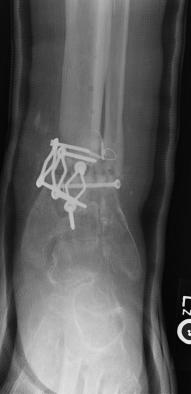

Post-corrective surgery X-Rays of the damaged right & left legs / ankles

The first two x-rays show Liam’s left ankle and pelvis prior to the accident. For comparison purposes it is interesting to see the

differences. The next x-rays were taken after the corrective surgery performed by Dr. Armendariz. Noticed that Dr. Armendariz has used tibia

bracing and also aligned the bone fragments of the left leg so that they could heal in the proper orientation. The external fixation has been

removed and Liam’s left foot has been returned to a more natural alignment.